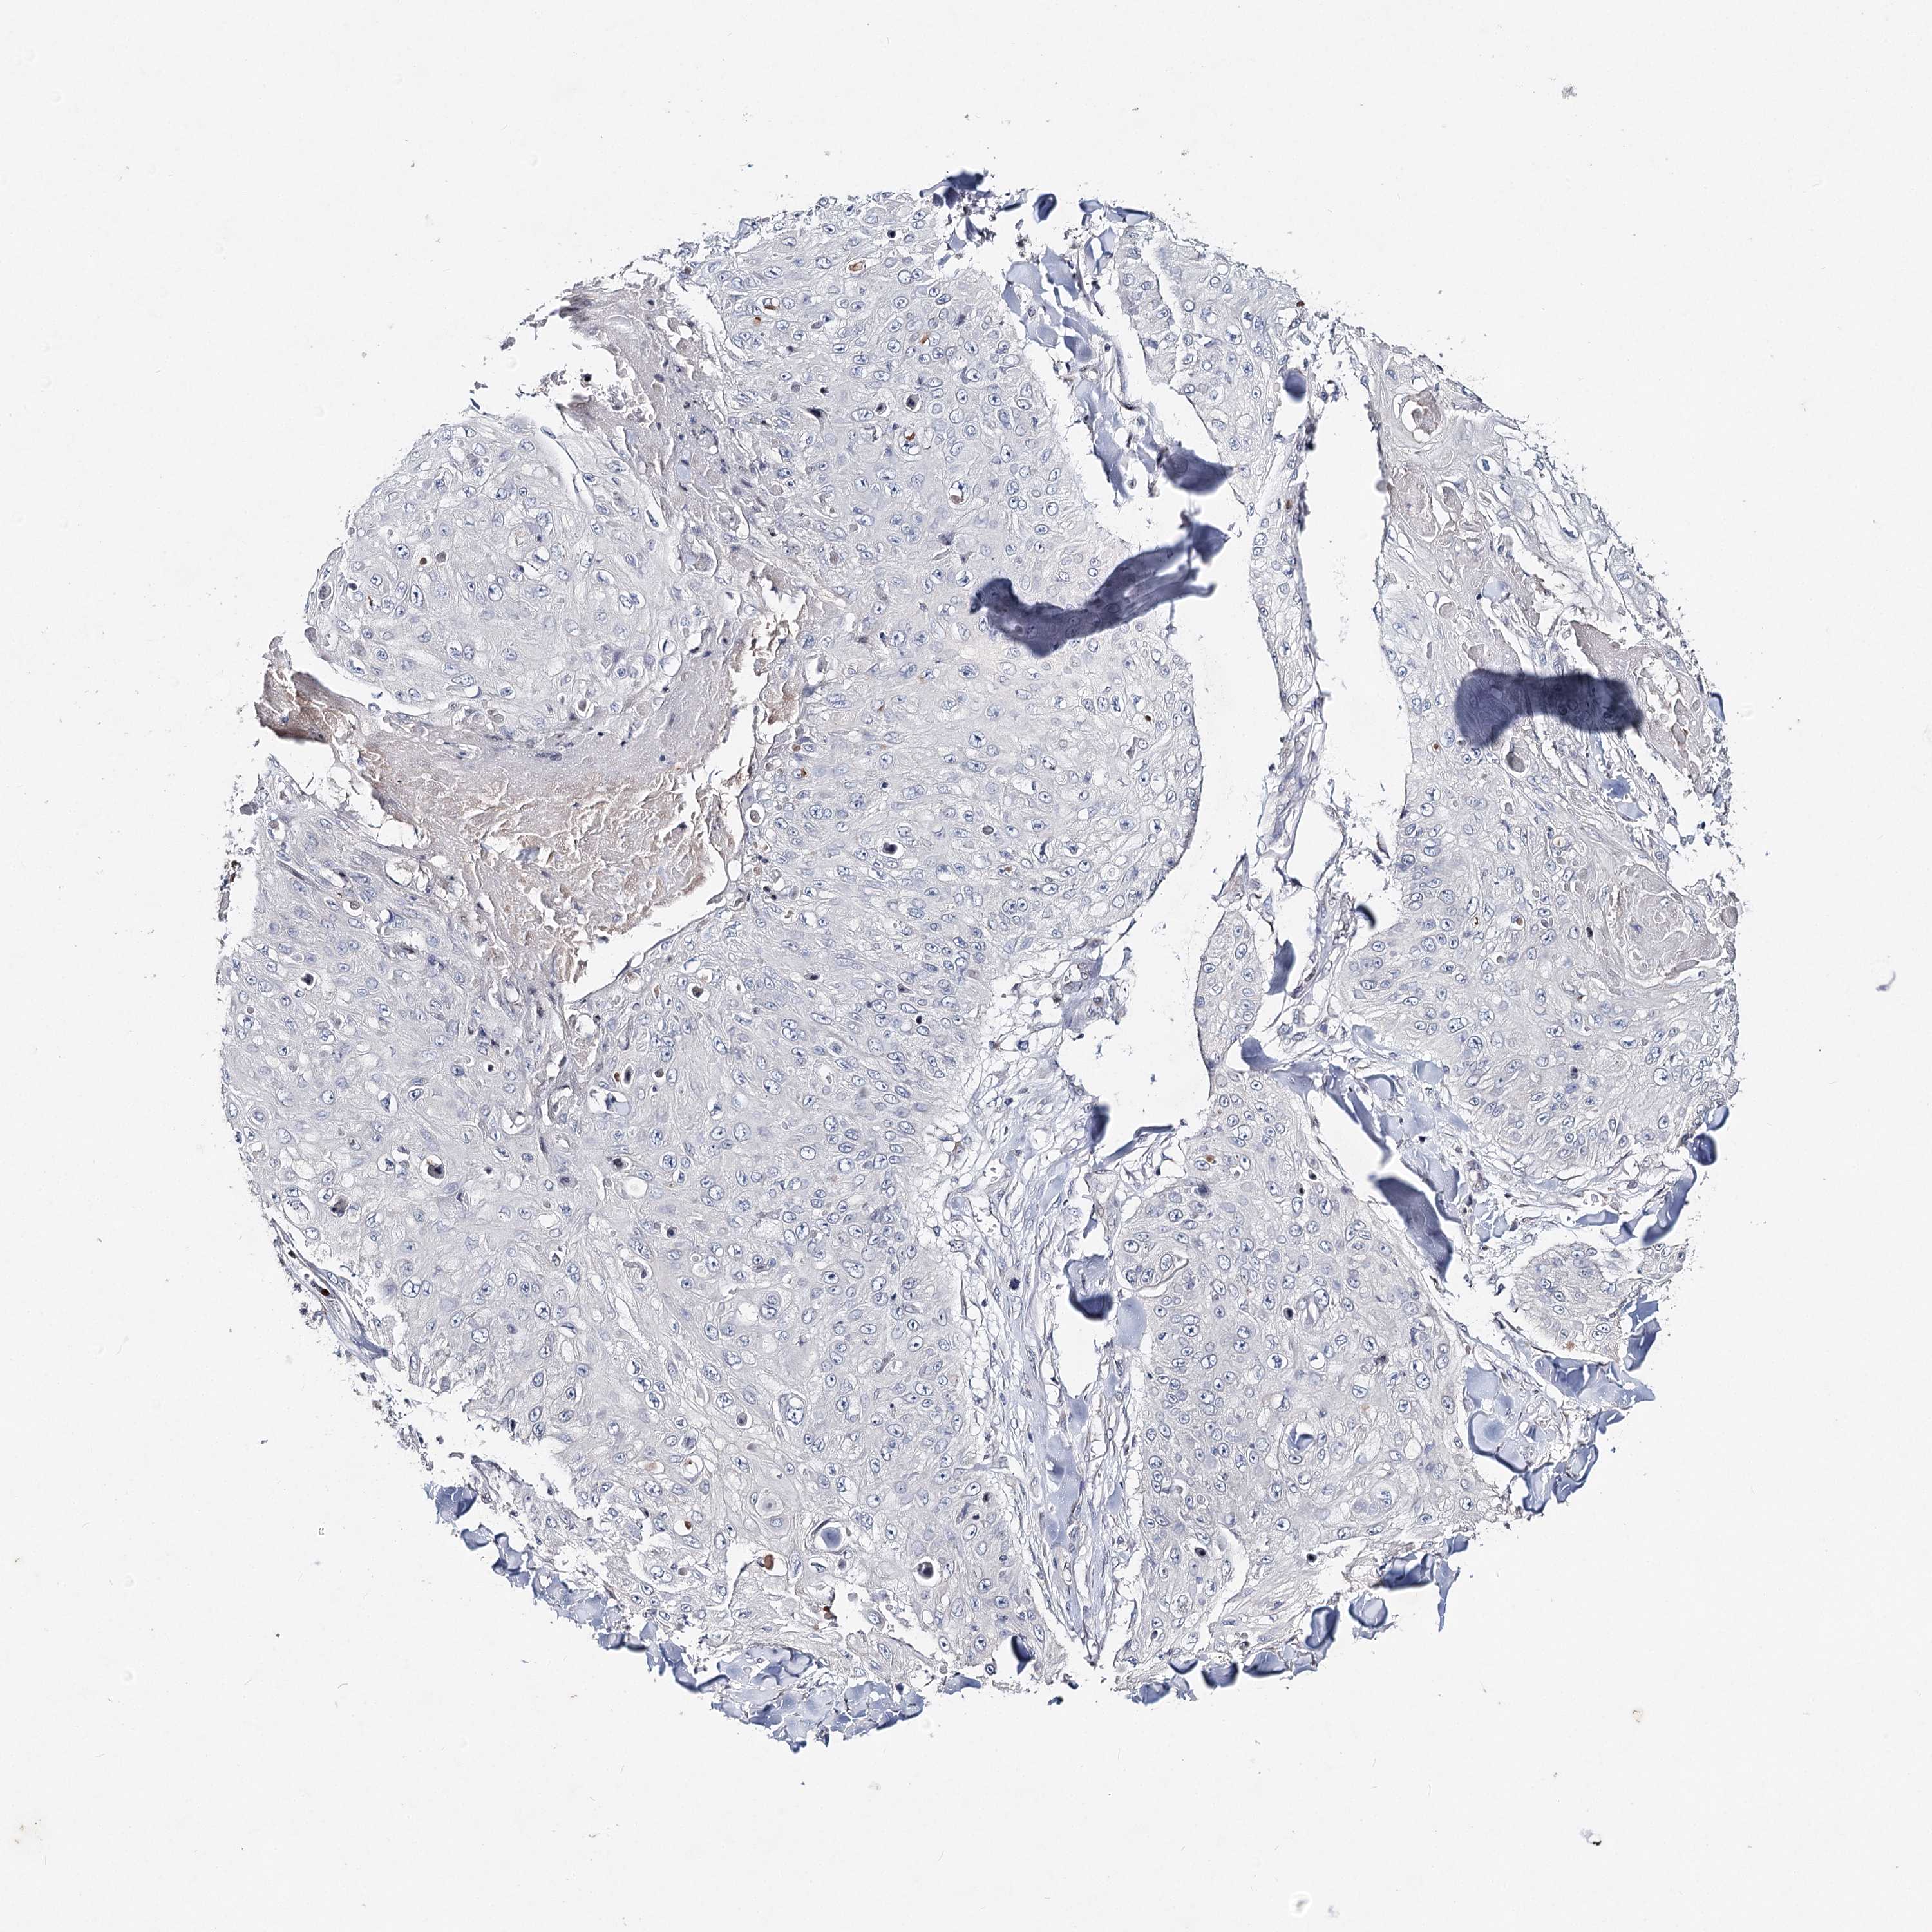

SKIN CANCER - Protein expressioni

A mouse-over function shows sample information and annotation data. Click on an image to view it in a full screen mode. Samples can be filtered based on level of antibody staining by selecting one or several of the following categories: high, medium, low and not detected. The assay and annotation is described here.

Antibody stainingi

Antibody staining in the annotated cell types in the current human tissue is reported as not detected, low, medium, or high, based on conventional immunohistochemistry profiling in selected tissues. This score is based on the combination of the staining intensity and fraction of stained cells.

Each image is clickable and will lead to virtual microscopy that enables deeper exploration of all samples and also displays staining intensity scores, fraction scores and subcellular localization as well as patient and tissue information for each sample.

Antibody HPA038449

Staining

High

Medium

Low

Not detected

Intensity

Strong

Moderate

Weak

Negative

Quantity

>75%

75%-25%

<25%

None

Location

Nuclear

Cytoplasmic/membranous

Cytoplasmic/membranous,nuclear

Squamous cell carcinoma in situ, NOS

Squamous cell carcinoma, NOS

Basal cell carcinoma

Adnexal tumor, benign